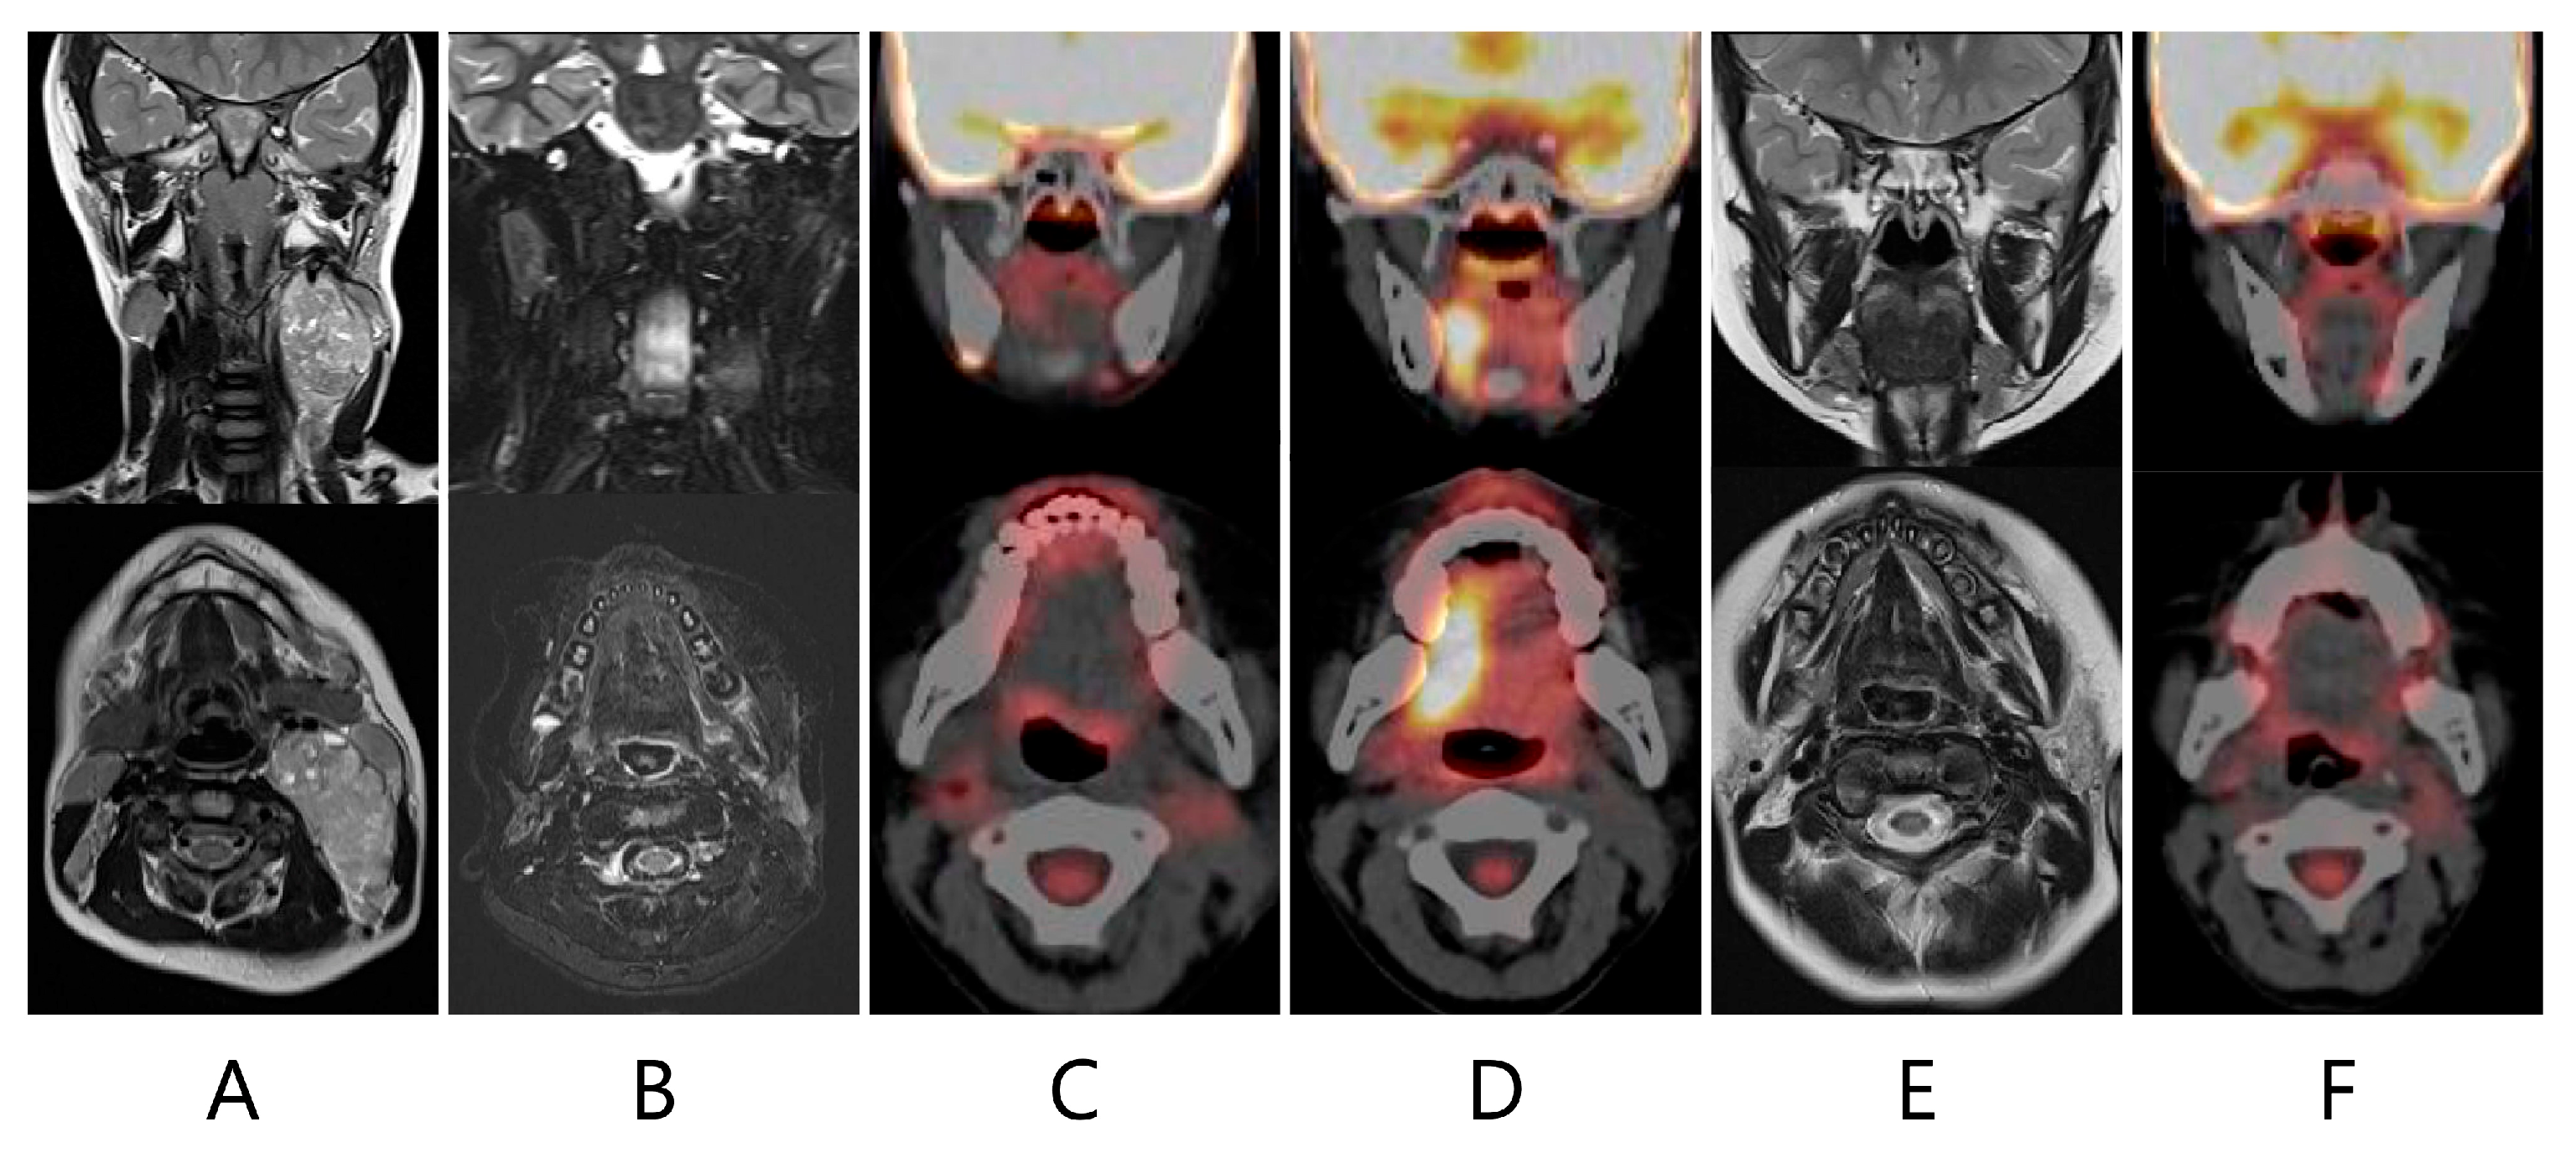

False-Positive Asymmetrical Tongue Muscle 18F-FDG Uptake in Hypoglossal Nerve Paralysis Following Lymph Node Dissection in a Pediatric Patient with Malignant Rhabdoid Tumor of the Neck

Matsumoto, Y.; Matsui, M.; Makidono, A.; Makimoto, A.; Yuza, Y. False-Positive Asymmetrical Tongue Muscle 18F-FDG Uptake in Hypoglossal Nerve Paralysis Following Lymph Node Dissection in a Pediatric Patient with Malignant Rhabdoid Tumor of the Neck. Children 2024, 11, 348. https://doi.org/10.3390/children11030348